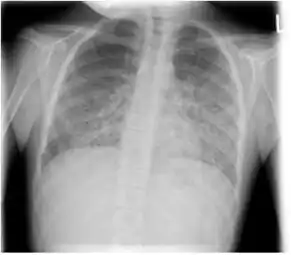

The diagnosis can be confirmed by the characteristic appearance of the chest X-ray and an arterial oxygen level (PaO2) that is strikingly lower than would be expected from symptoms. Gallium 67 scans are also useful in the diagnosis. They are abnormal in about 90% of cases and are often positive before the chest X-ray becomes abnormal. Chest X-ray typically shows widespread pulmonary infiltrates. CT scan may show pulmonary cysts (not to be confused with the cyst-forms of the pathogen).

- Chest X-ray of increased opacification (whiteness) in the lower lungs.

- These chest radiographs are of two patients. Both show ground glass opacities. The left X-ray shows a much more subtle ground-glass appearance while the right X-ray shows a much more gross ground-glass appearance mimicking pulmonary edema.[6]

- X-ray of a cyst in pneumocystis pneumonia[6]